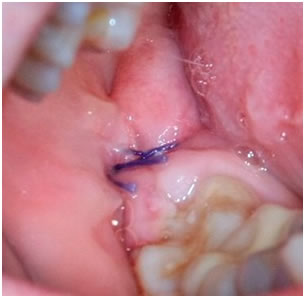

Последствия после удаления зуба мудрости

Что делать, если после удаления зуба воспалилась десна, появился отек или поднялась температура? Все перечисленное выше – это осложнения, которые возникают у многих людей. Иногда последствия после удаления зуба мудрости проходят сами собой, а иногда приходится обращаться к хирургу, чтобы он провел экстренное хирургическое вмешательство. Почему же все идет не так, как хотелось бы? Когда надо поднимать панику и нервничать?

Гной

Он возникает из-за инфицирования. Порой, пациенты пренебрегают процедурой гигиены полости рта. Иногда в лунке остается осколок зуба, который надо удалить, как можно быстрее. Повторный визит к стоматологу необходимость, и не стоит откладывать его.